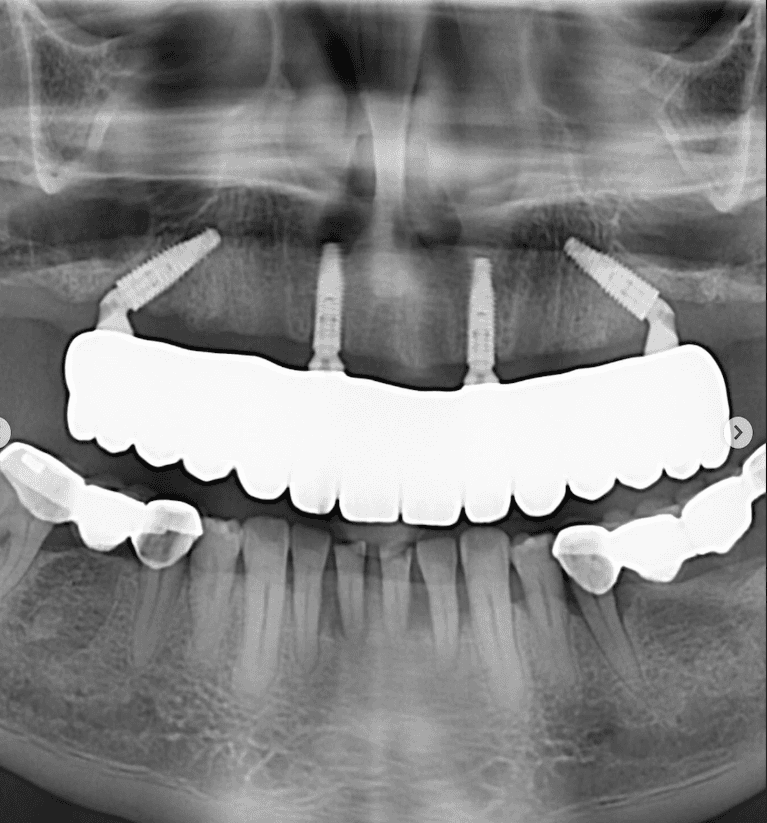

Upper & Lower, All on 4 fixed implant teeth with finals. Patient went home with temp fixed teeth the same day.